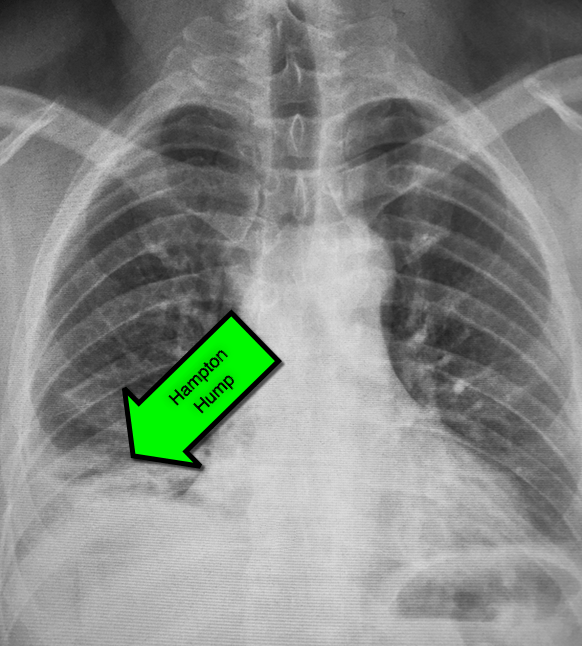

Pulmonary Embolism Chest X Ray Can Chest X Ray Detect Pulmonary Embolism This noninvasive test shows images of your heart and lungs on film. The first signs of pulmonary embolism are usually shortness of breath and chest pains that get worse if you exert yourself or take a deep breath. A highly suggestive indicator of septic pulmonary embolism is the “feeding vessel sign”, which is characterized by a discernible vessel. If you. Can Chest X Ray Detect Pulmonary Embolism.

Pulmonary Thromboembolism Undergraduate Diagnostic Imaging Fundamentals Can Chest X Ray Detect Pulmonary Embolism A highly suggestive indicator of septic pulmonary embolism is the “feeding vessel sign”, which is characterized by a discernible vessel. This noninvasive test shows images of your heart and lungs on film. The first signs of pulmonary embolism are usually shortness of breath and chest pains that get worse if you exert yourself or take a deep breath. If you. Can Chest X Ray Detect Pulmonary Embolism.